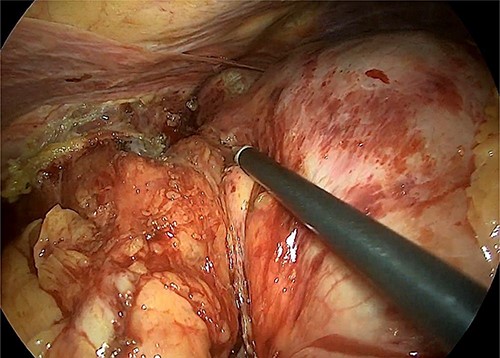

The hiatal region was dissected (Fig. 4). The gastric section was performed at the level of the pyloric antrum and the stomach at the level of the oeso-gastric junction. An intraoperative anatomopathological examination on the oesophageal section did not find any malignancy. A latero-lateral semi-mechanical gastrojejunal anastomosis was performed.

Intraoperative image that reveals the hiatal dissection and the proximity of the tumour with the cardia.